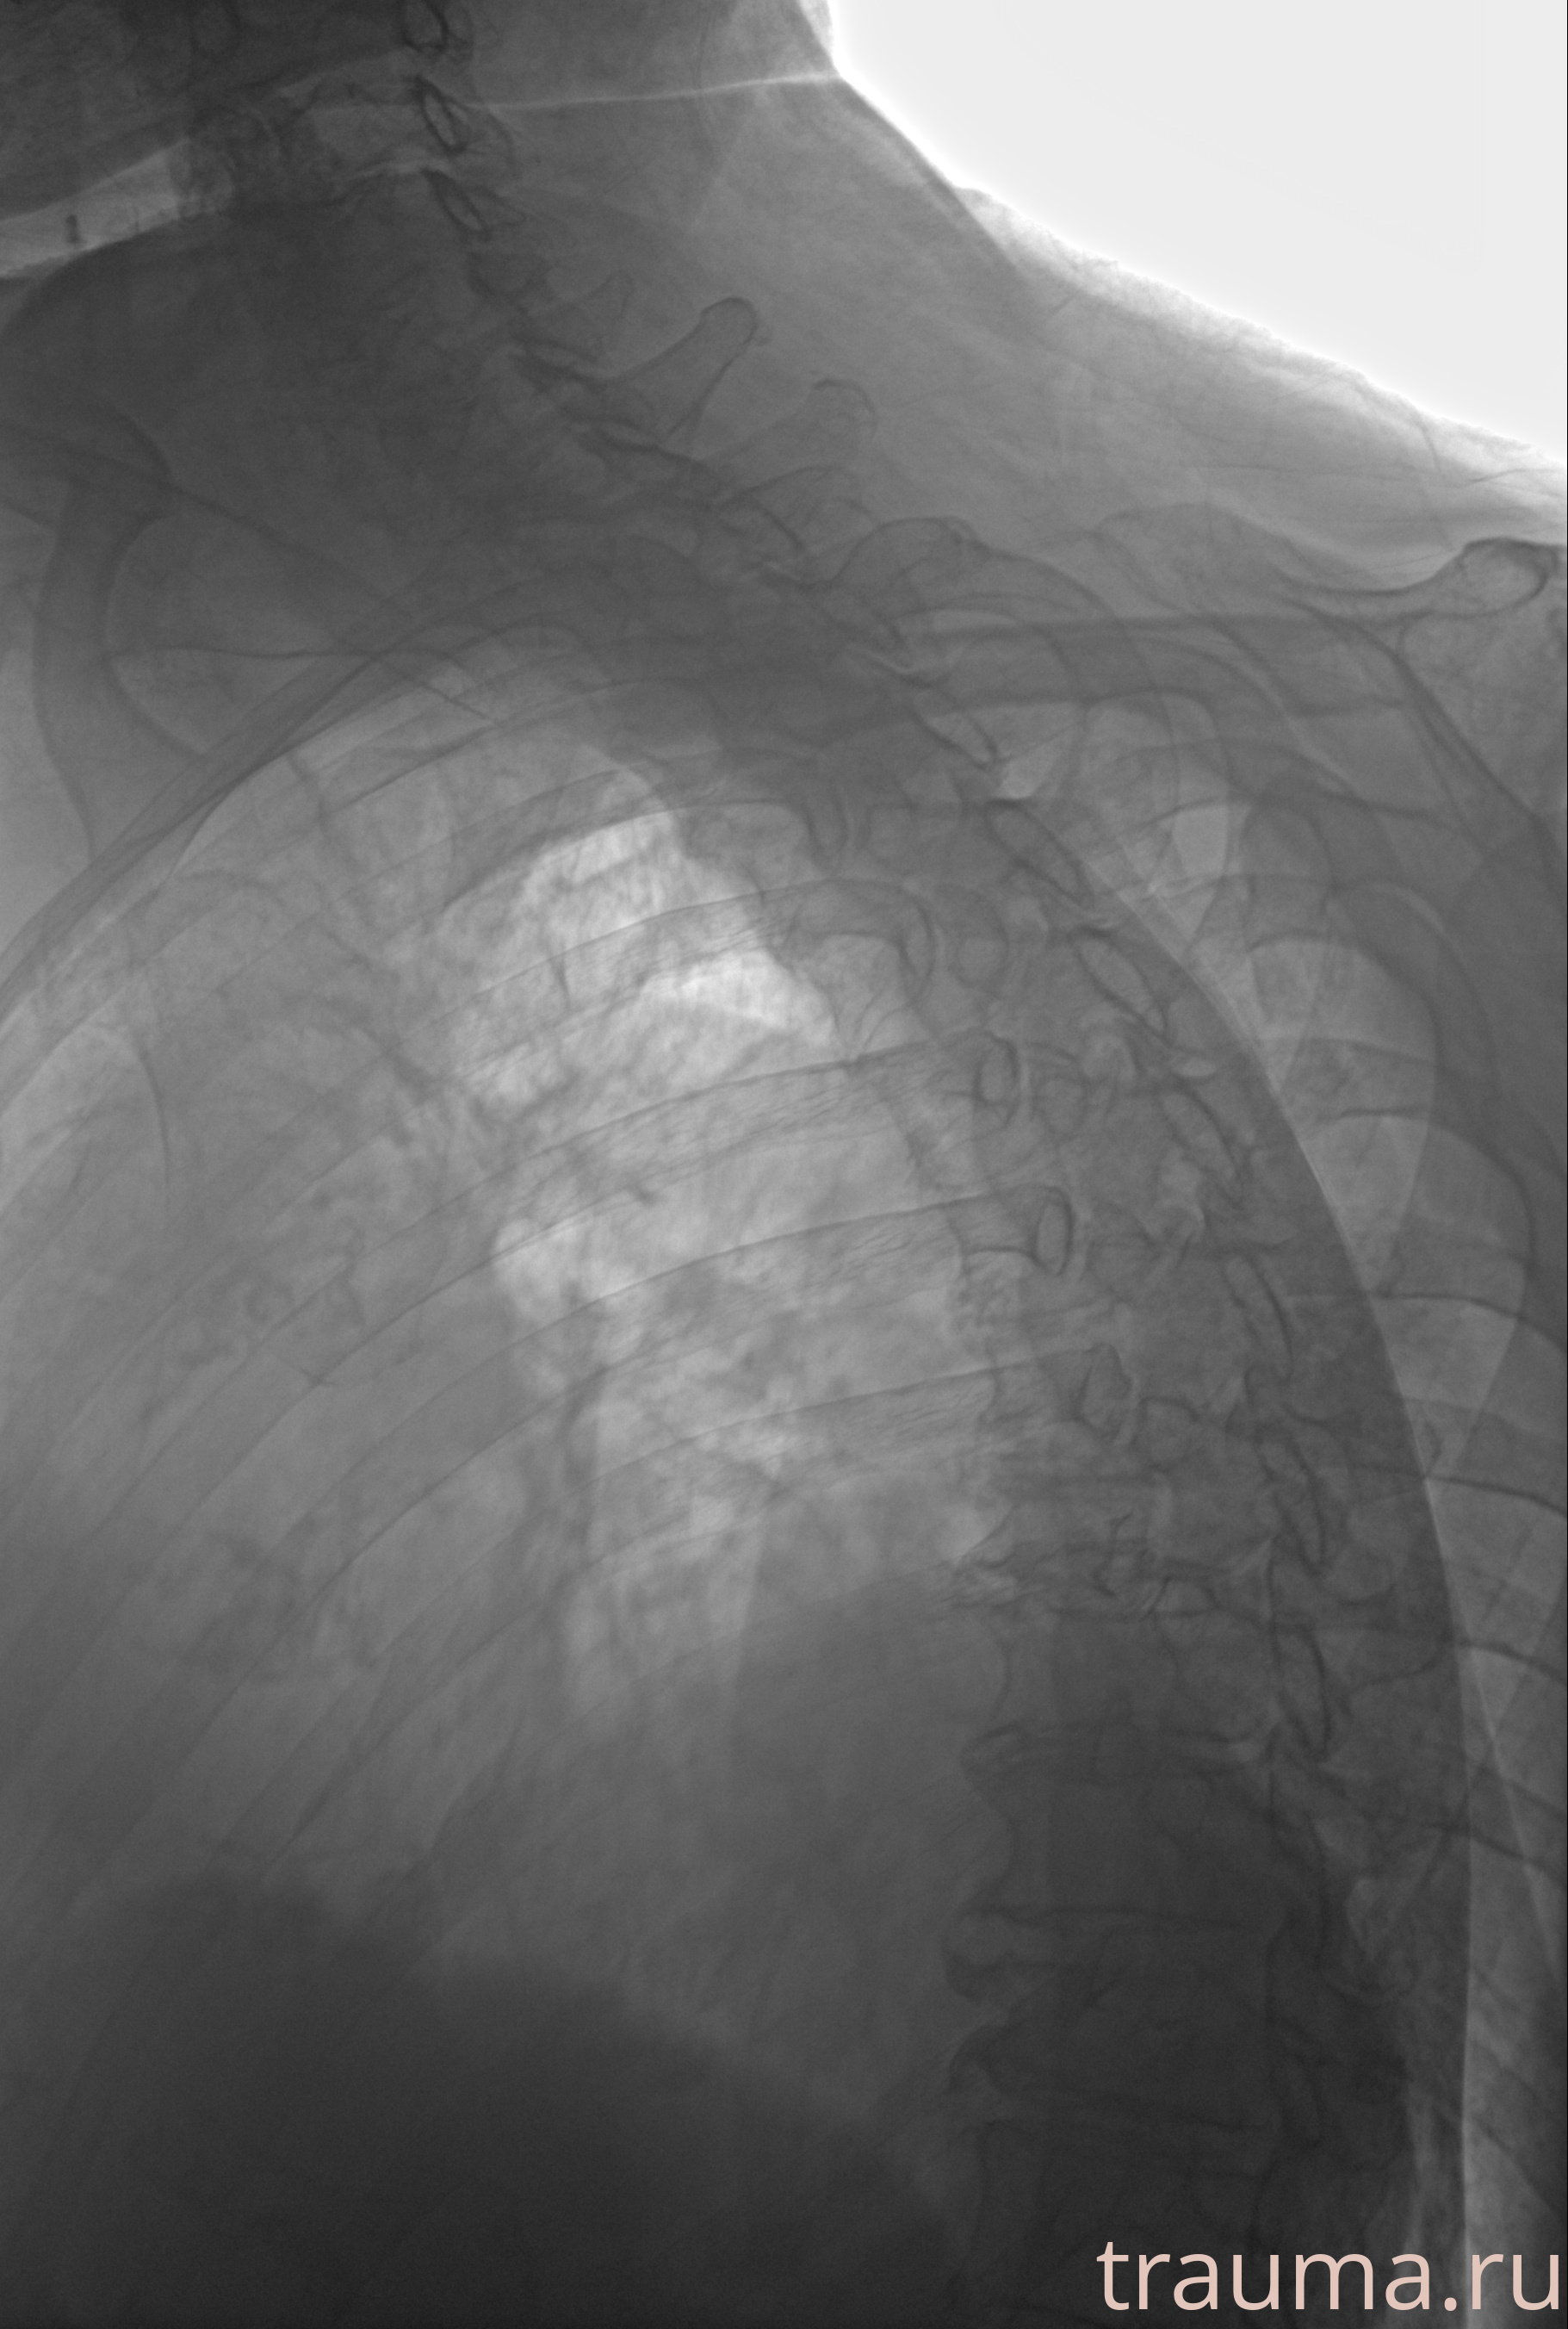

Рентгенограммы

Рентген на дому: по вашему адресу приезжает врач-рентгенолог, травматолог-ортопед с мобильным рентгеновским аппаратом, проводит диагностику травмы или заболевания, делает необходимые рентгенограммы, дает рекомендации по дальнейшему лечению. Получить качественные снимки в домашних условиях возможно благодаря уникальной методике, разработанной МосРентген Центром для института  Склифосовского